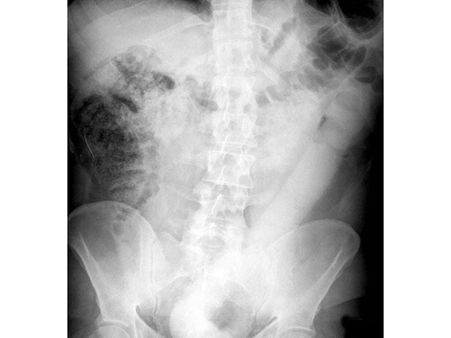

Even though the doctors on examination found out the size of the dildo to be 23 inches which is a 2-feet-long sex toy, the man was not in much stress as he complained of just mild abdominal pain. He was later referred to the endoscopy unit.

The doctors in their journal revealed that multiple tools were used to remove the foreign object from the body. But due to the massive size and the smooth finishing of the sex toy, it was a task to remove it without causing much damage to the internal organs.

They tried using a wire loop device which is generally used to remove polyps and displaced it with a dilating balloon which they later grabbed with forceps. But all the attempts failed, and hence the doctors resorted to inventing a new tool.

To avoid further internal damage, the doctors decided to create a new tool to remove the object. They built a "home-made" device in which they used a medical wire that was used to push a stent tube. The device was rigid enough to loop around the sex toy, and it was used to pull the dildo away from the colon walls easily.